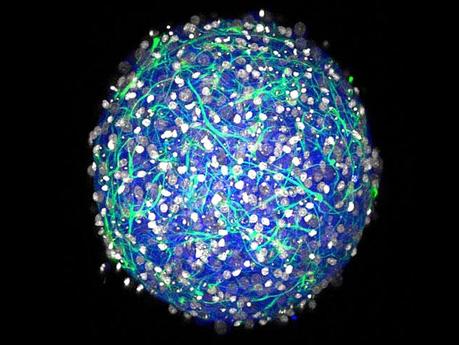

Pare chi siamo giunti a una svolta, almeno me lo auguro, un gruppo di ricercatori degli Stati Uniti ha sviluppato dei "mini cervelli" in laboratorio da cellule umane, sostenendo che sono un buon sostituto per testare nuovi farmaci, così facendo questi "mini cervelli" potranno essere replicati e di conseguenza la sperimentazione sugli animali non sarà più necessaria!

Evviva Dio, era ora e speriamo si concretizzi come pratica definitiva, per ora sappiamo che questo nuovo metodo di sperimentazione dovrebbe diventare operativo entro quest'anno, e così si risparmieranno la vita e le sofferenze anche a oltre 100 milioni di topi e ratti che ogni anno sono torturati per fare test.